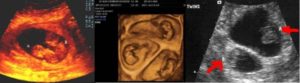

4. Ультразвуковое исследование — самый достоверный способ увидеть и определить, какая у женщины беременность, более точный срок беременности, размеры плодов и все патологии, существующие у двоих эмбрионов (если таковые имеются). А также при помощи данного метода возможно определить однояйцевая или разнояйцевая беременность наблюдается у женщины.

Двойню на УЗИ можно увидеть и определить уже на 4-5 неделе беременности. Как правило, однояйцевые близнецы определяются позже, чем разнояйцевые (не раньше 12 недели).

Самый верный способ выяснить количество эмбрионов – это дождаться первого УЗИ. В муниципальных женских консультациях оно проводится на 12 – 14 неделях во время первого скрининга.

По УЗИ двойня видна на 8 акушерской неделе (6 неделя от зачатия)

Самый ранний срок, когда по УЗИ различим плодный мешочек – это 4 недели и 3 дня при условии, что менструальный цикл женщины 28 – 30 дней. Но двойню пока никакой аппарат не определит. Это возможно лишь на 8 акушерской неделе.